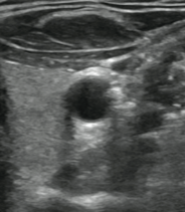

[10] Example ultrasound images with speckle noise(both), downward attenuation(both), shadows(blue regions left) and reverberation artefacts (blue lines right)

As is the case for many coherent imaging systems (systems in which waves can interfere with each other), the sensor unintentionally picks up unwanted signals that may come from the environment or the transducer itself. This leads to random overlaying patterns in the image. Speckle Noise in particular is the noise generated by the random scattering of transducer sound waves through the tissue. We can see this effect in both of the above images.

Acoustic Shadows and Downward Attenuation

Highly reflective tissue or materials reduce the amount of transmitted sound waves that would pass to tissue more distant to the transducer. This leads to so-called shadowing regions that are particularly prune to noise signals coming from the surrounding tissue. Since sound waves will be dampened while passing through any kind of material, even a body with equal impedance will produce an image with a continuously darker growing shadow. This effect is called downward attenuation and can also be seen in the above images that both get darker in downward direction. An example for shadows can be seen inside the blue coloured circles in the left image.

Reverberation Artefacts

In addition to shadowing regions, two reflective objects can also cause reverberation artefacts when light bounces back and forth between them, causing a repeating pattern. In the right image they are highlighted with blue color and generally appear as repeating pattern with equal distance.